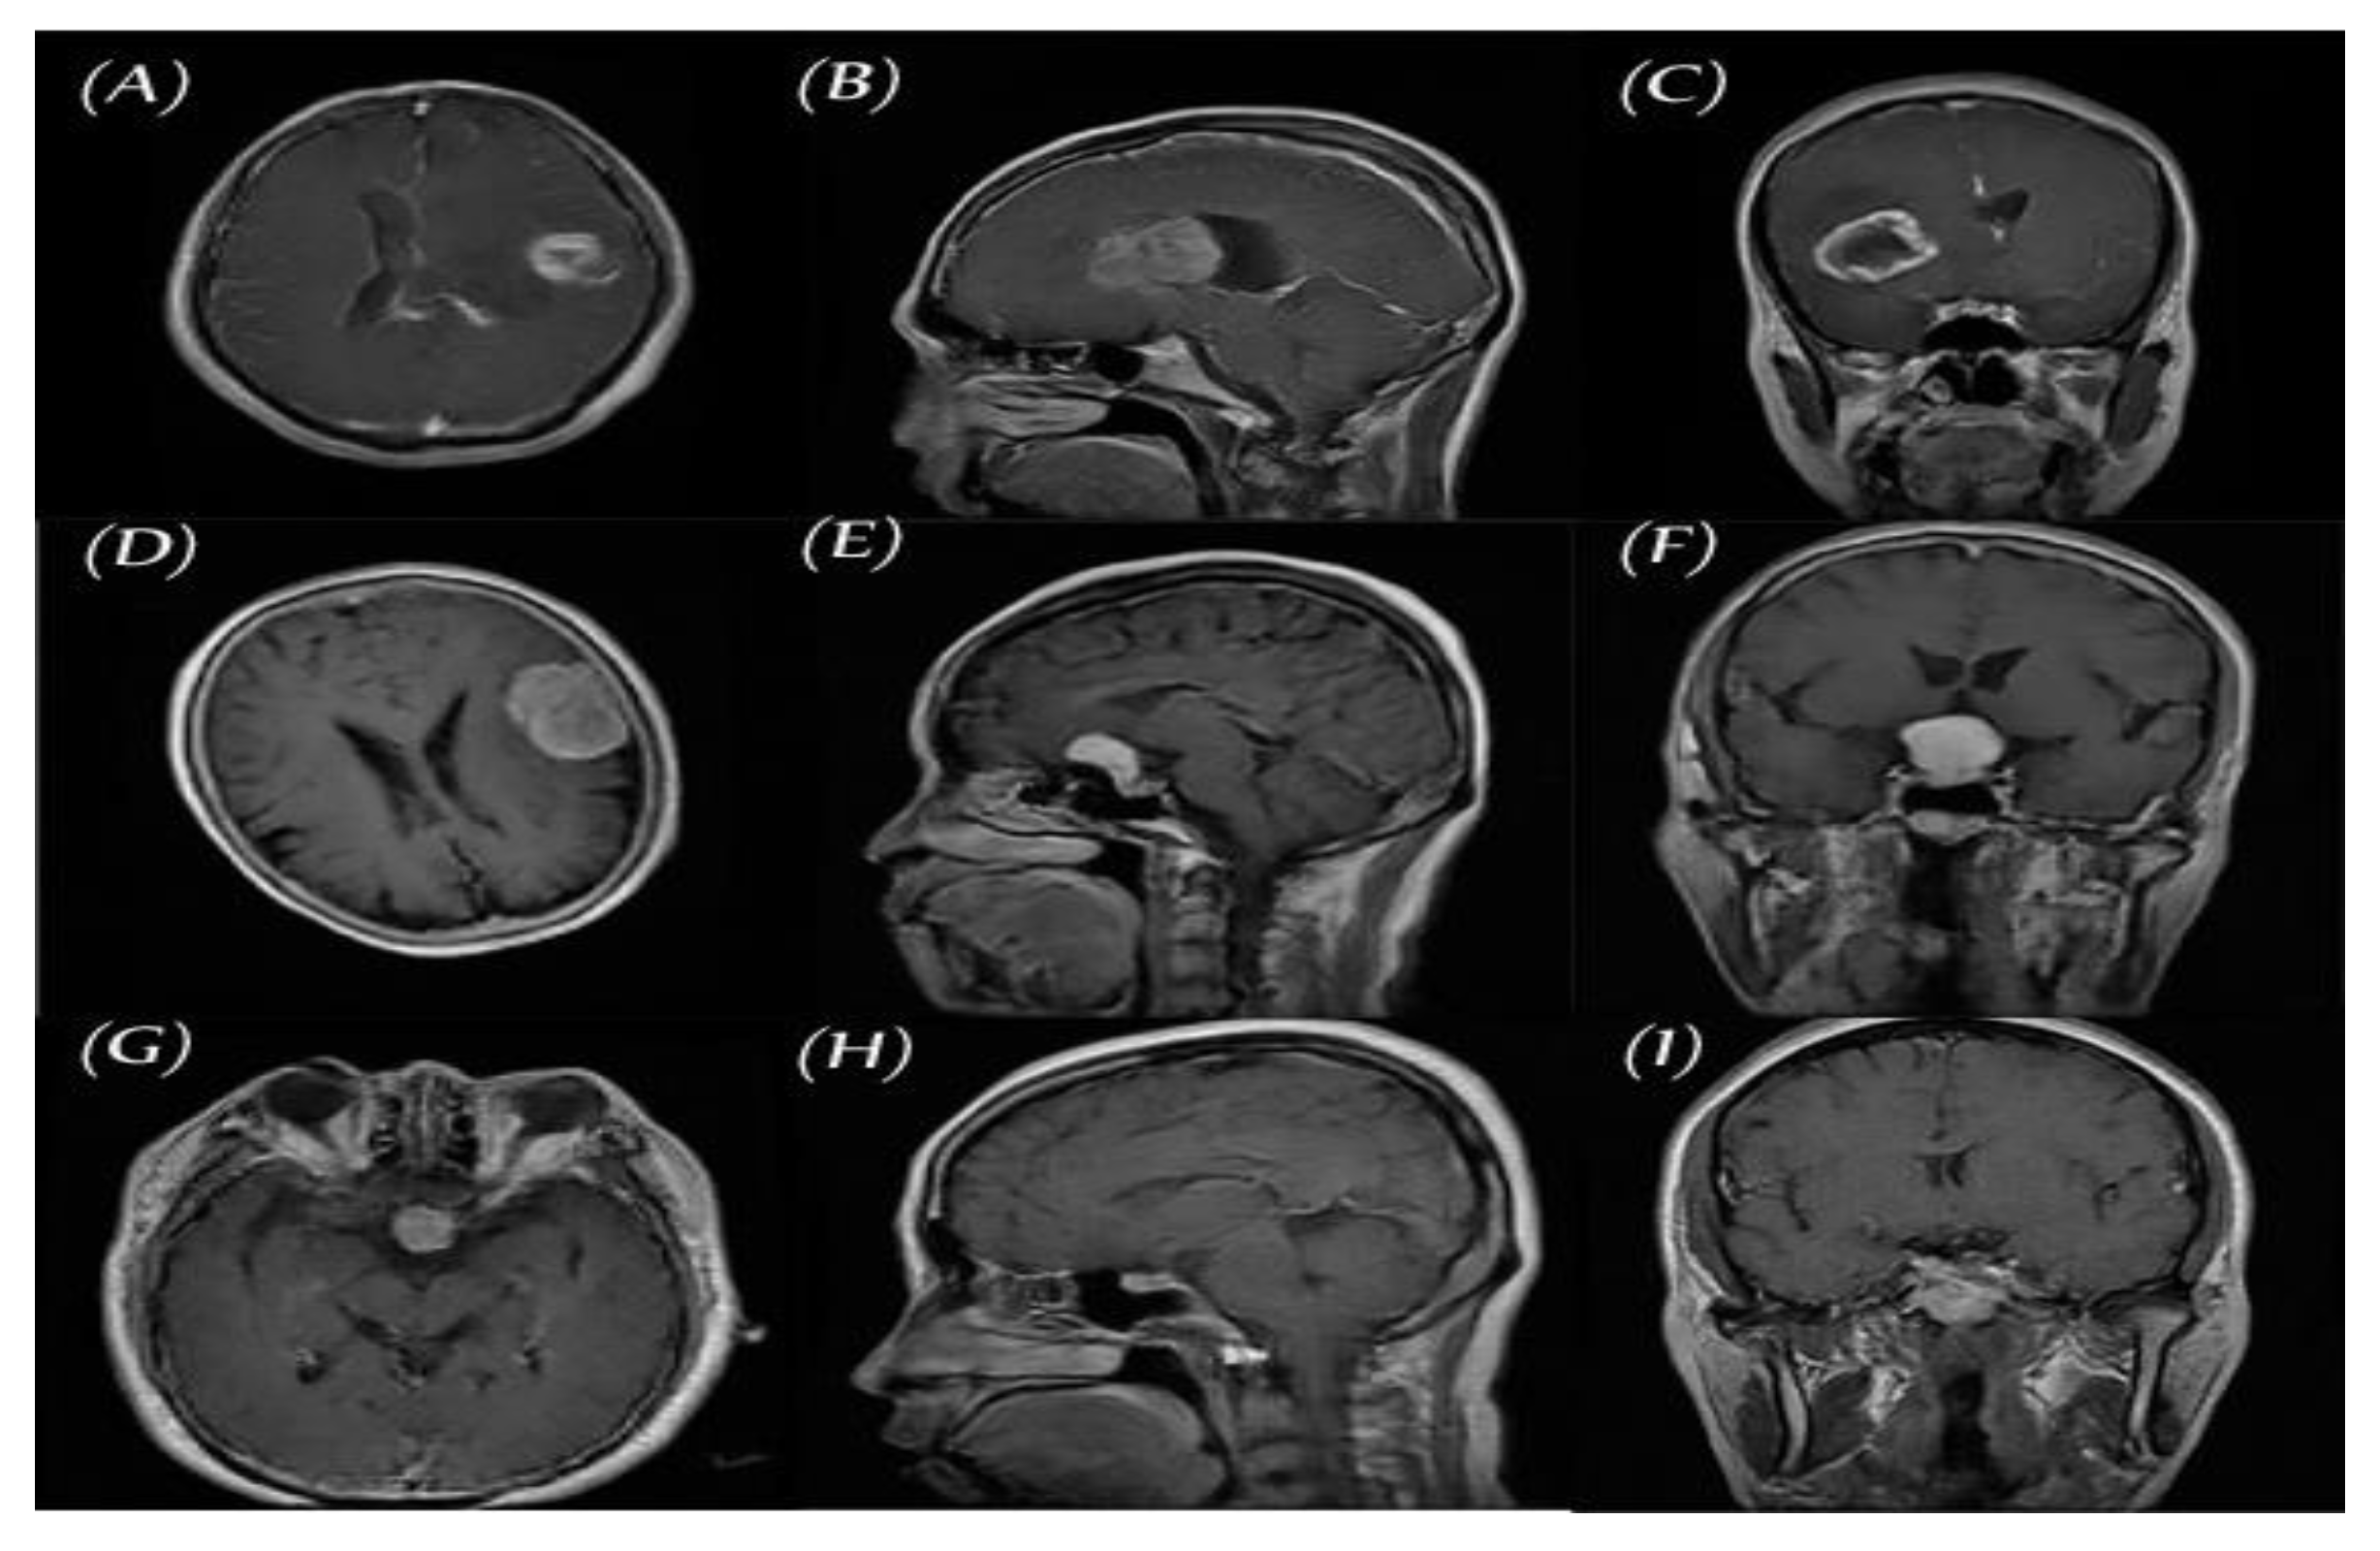

2.1. Data set for the Study

2.2.2. PGGAN-Based Data Augmentation